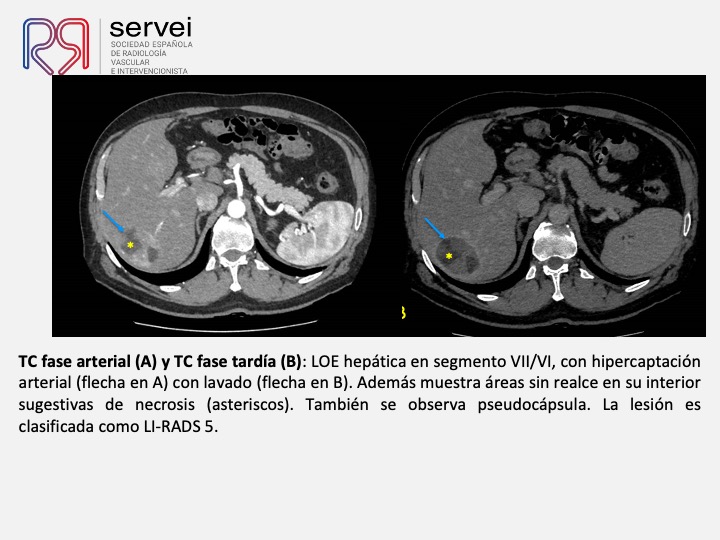

Radioembolización de hepatocarcinoma con 166-Holmio. Utilidad en pacientes con hepatocarcinoma en estadio inicial (BCLC A)